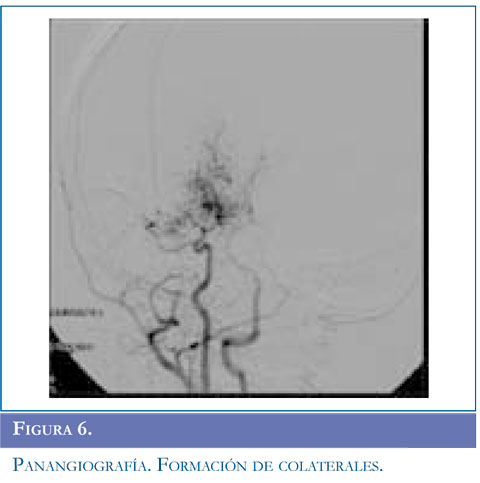

Se inició manejo con carbamazepina, se solicitó RM simple reportada con lesión sugestiva de tipo desmielinizante que compromete sustancia blanca y centros semiovales, sin realce al contraste. Ante la recurrencia de evento de hemiparesia contralateral se realizó RM de control que mostró aumento en el número de las lesiones. Se estudió enfermedad neu-rometabólica con compromiso de sustancia blanca con normalidad en ácidos orgánicos, aminoácidos en orina, acido láctico, ácidos grasos de cadena larga. Presentó nuevo evento de hemiparesia izquierda con estatus convulsivo focal se realizó TAC de cráneo que mostró ACV isquémico parietooccipital derecho, se solicitó panangiografía y doppler carotídeo. Angiografía con compromiso bilateral con hallazgos sugestivos de enfermedad de Moyamoya, y doppler trascraneal hallazgos compatibles con hipoplasia proximal de arterias cerebrales media y anterior izquierda compensado con flujo colateral a través de comunicante posterior izquierda. Valorado por neurocirugía no consideraron manejo quirúrgico. El paciente ha continuado presentando episodios transitorios de ACV. Figuras 4, 5 y 6

Para el estudio de esta enfermedad ante la sospecha clínica se deben solicitar estudios radiológicos como tomografía computarizada de cráneo (TAC) evidenciando áreas pequeñas de hipodensidad que sugieren hemorragia o isquemia en región cortical, ganglio basal, profundidad de sustancia blanca o región periventricular; sin embargo, la TAC puede ser normal si el paciente presenta un evento isquémico transitorio. En todos los pacientes de esta serie, se solicitó TAC encontrandose lesión focal secundaria al evento vascular en regiones subcorticales y gangliobasales. La disponibilidad de RM y angiografía por RM se ha convertido en el método diagnóstico del síndrome de Moyamoya. Un infarto cerebral agudo es más probable que se detecte con el uso de imagen por difusión, un infarto cerebral crónico se observa en RM en T1-T2. El flujo sanguíneo cortical disminuido se observa en la secuencia FLAIR como una señal lineal intensa que sigue la forma de los surcos llamado "signo de la hiedra" (14). Los hallazgos más frecuentes en RM son reducción del flujo de la arteria carótida interna, arteria cerebral anterior y media hasta llegar a ausencia de flujo sanguíneo en ganglios basales y tálamo con formación de vasos colaterales; en este informe el examen confirmatorio se realizó con angiografía, se debe realizar estudio de 5 o 6 vasos que incluyan arterias carótidas externas, carótidas internas y 1 ó 2 arterias vertebrales según colaterales que se presenten. El diagnóstico definitivo se basa en el aspecto arteriográfico caracterizado por estenosis de la arteria carótida interna a nivel distal, extendiéndose a la región proximal y media (15). La severidad de la enfermedad se clasifica de I a VI estadios de progresión según el sistema de clasificación de Suzuky (16) (Tabla 1). En los casos presentados el grado de estatificación fue IV y V mientras que en la serie de González (5) existieron varias presentaciones I, III y VI; Galicchio (6) presentó casos en estadio II a III.